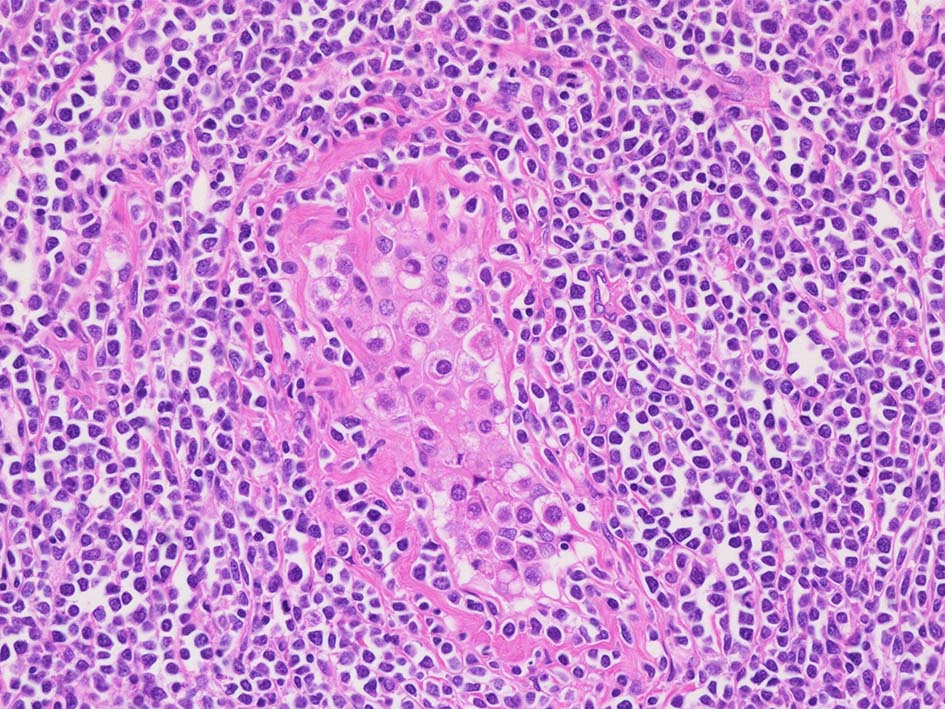

光顕所見; リンパ腫により, 少なくとも一部の領域の精細管が消失する. 末梢の領域では精細管の間質にリンパ腫細胞が浸潤する. ほとんどの場合、腫瘍細胞は精細管に侵入, 精細管の周辺を占め、生殖細胞とセルトリ細胞を中央に変位させるか, または精細管を完全に占拠してしまう.

精細管は浸潤により萎縮, 消失. びまん性にcentroblasts/immunoblastsの増殖が認められる. 腫瘍細胞間に軽度の線維化がある.

DLBCLとは細胞の大きさや細胞所見が異なっている. 精細管への浸潤, 占拠所見がある.

精細管の多くがスペアされ, 間質にlymphoid cellsが密に浸潤している. わずかな精細管に浸潤が認められ萎縮や破壊像が認められる. 精細管において Lymphoepithelial lesion(LEL)に似た所見がある.